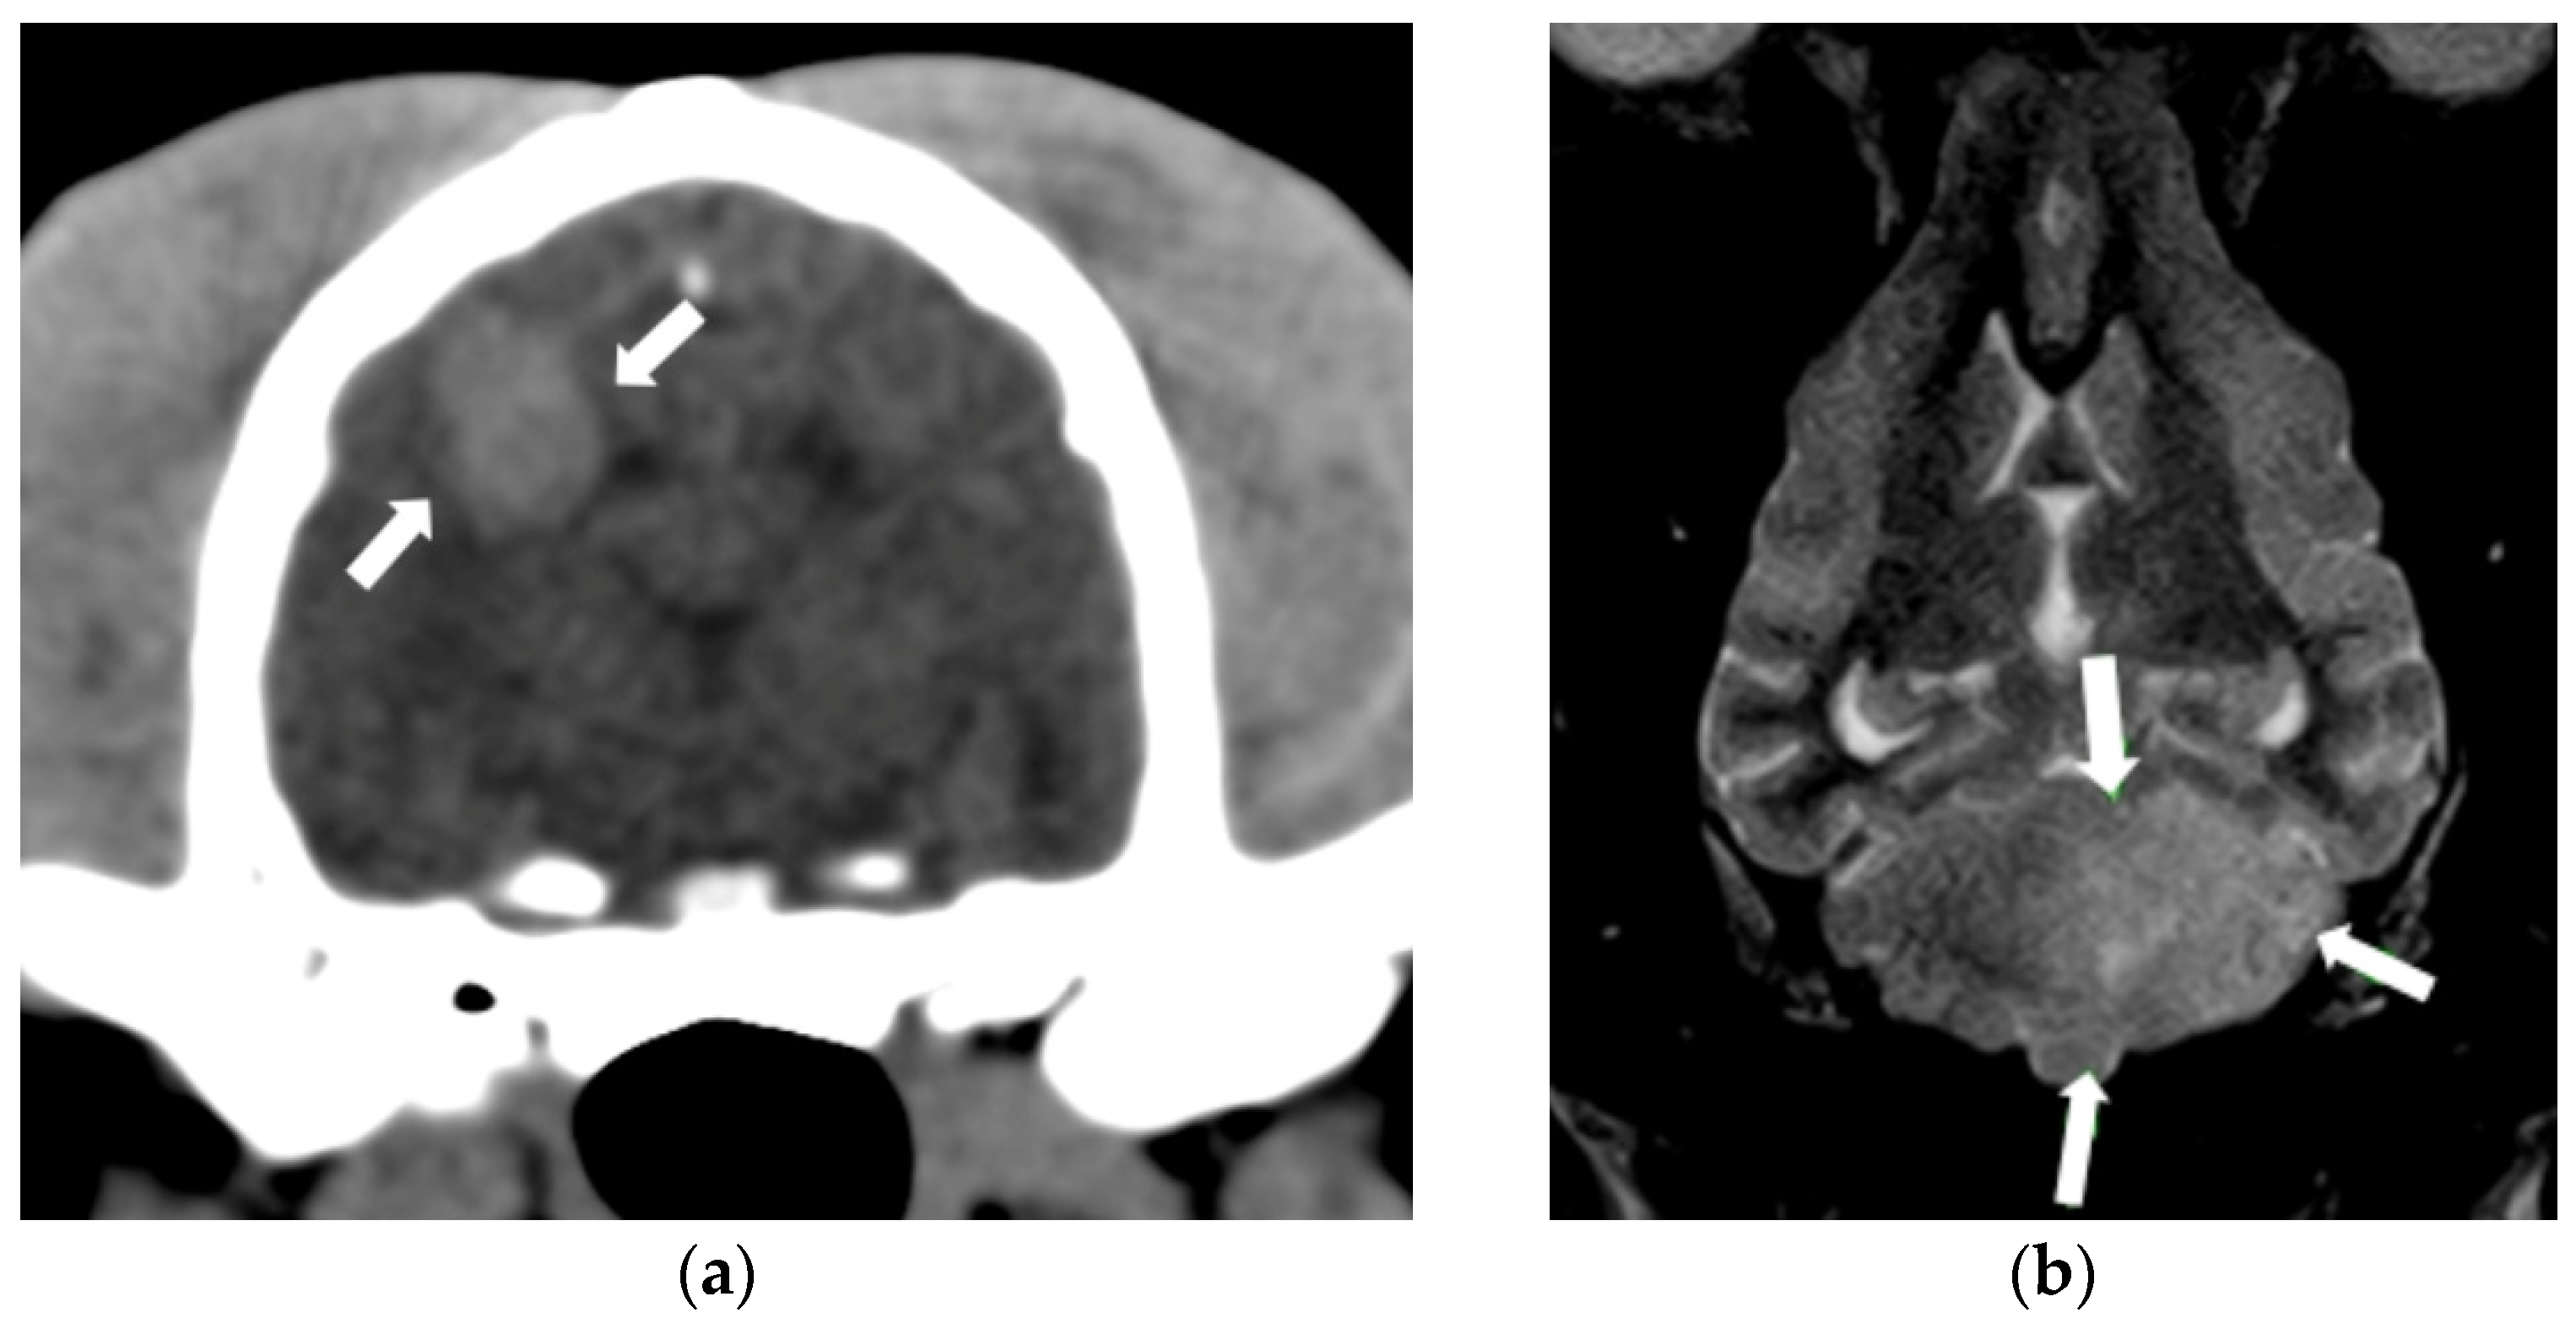

2.1. Intracranial Neoplasia

2.2. Cerebrovascular Disease

- Stadler, K.L.; Ruth, J.D.; Pancotto, T.E.; Werre, S.R.; Rossmeisl, J.H. Computed Tomography and Magnetic Resonance Imaging Are Equivalent in Mensuration and Similarly Inaccurate in Grade and Type Predictability of Canine Intracranial Gliomas. Front. Vet. Sci. 2017, 4, 157. [Google Scholar] [CrossRef]

- Cherubini, G.B.; Mantis, P.; Martinez, T.A.; Lamb, C.R.; Cappello, R. Utility of Magnetic Resonance Imaging for Distinguishing Neoplastic from Non-Neoplastic Brain Lesions in Dogs and Cats. Vet. Radiol. Ultrasound 2005, 46, 384–387. [Google Scholar] [CrossRef]

- Wolff, C.A.; Holmes, S.P.; Young, B.D.; Chen, A.V.; Kent, M.; Platt, S.R.; Savage, M.Y.; Schatzberg, S.J.; Fosgate, G.T.; Levine, J.M. Magnetic Resonance Imaging for the Differentiation of Neoplastic, Inflammatory, and Cerebrovascular Brain Disease in Dogs. J. Vet. Intern. Med. 2012, 26, 589–597. [Google Scholar] [CrossRef]

- Wisner, E.R.; Dickinson, P.J.; Higgins, R.J. Magnetic Resonance Imaging Features of Canine Intracranial Neoplasia. Vet. Radiol. Ultrasound 2011, 52, S52–S61. [Google Scholar] [CrossRef]

- Bentley, R.T. Magnetic Resonance Imaging Diagnosis of Brain Tumors in Dogs. Vet. J. 2015, 205, 204–216. [Google Scholar] [CrossRef]

- Arnold, S.A.; Platt, S.R.; Gendron, K.P.; West, F.D. Imaging Ischemic and Hemorrhagic Disease of the Brain in Dogs. Front. Vet. Sci. 2020, 7, 279. [Google Scholar] [CrossRef]